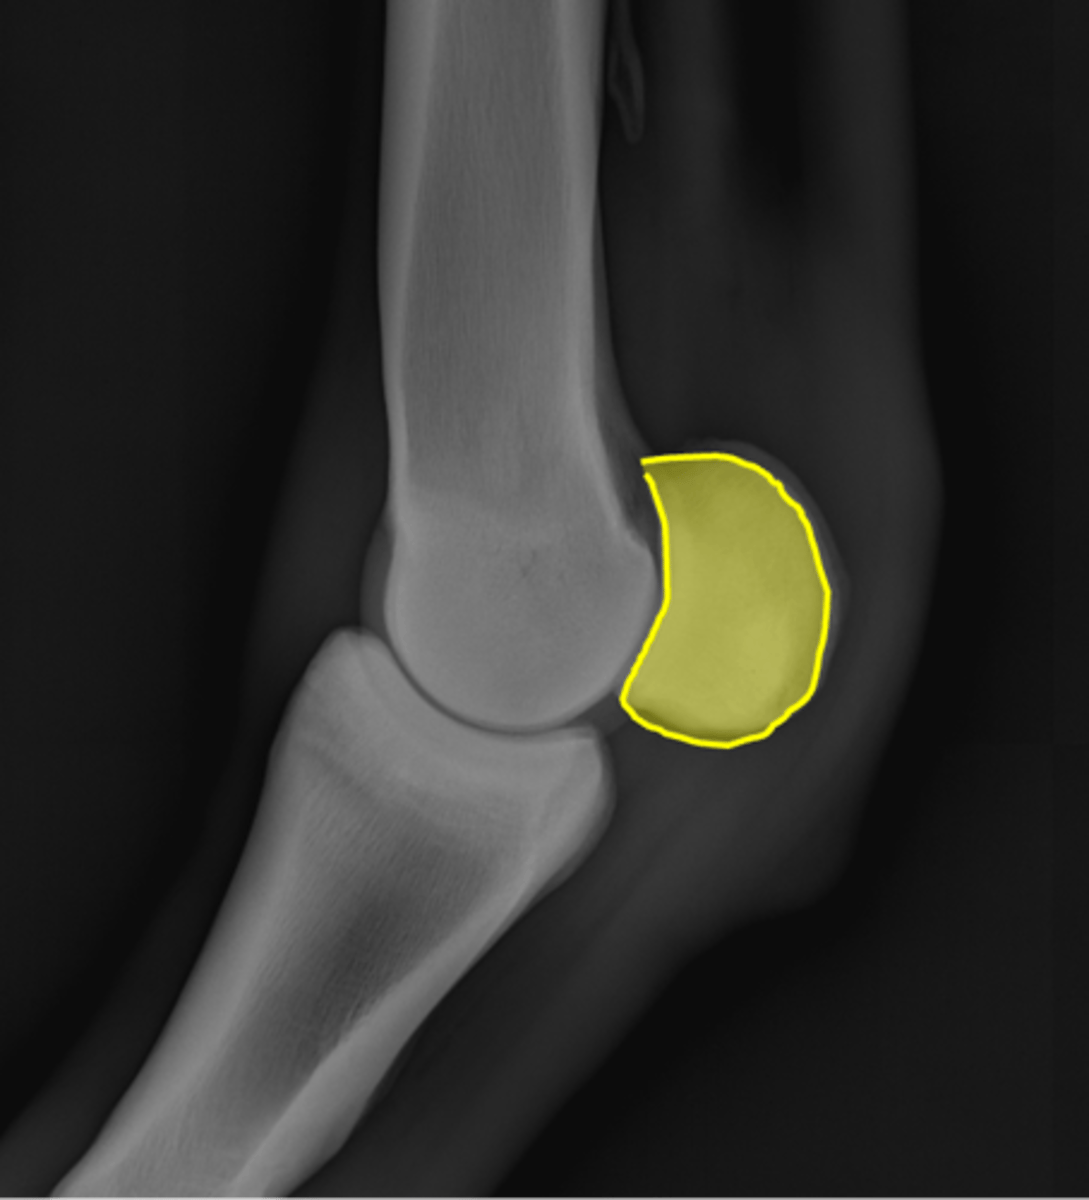

Proximal sesamoid bone

Sagittal ridge

Condyles of third metacarpal bone

Palmar process of P2

Proximal sesamoid bones

Sagittal ridge

Attachment of collateral ligaments

Proximal sesamoid bones

Palmar process of P1

Condyles of the third metacarpal bone